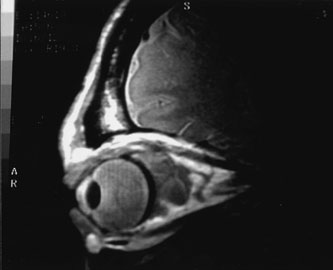

Fig. 6. Cavernous hemangioma. Axial magnetic resonance imaging demonstrates a well-defined, homogeneous intraconal mass that is isointense to muscle and gray matter on T1-weighted image (A), and hyperintense on T2-weighted image (B). Note the displacement of the optic nerve and indented posterior globe.